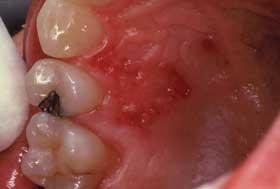

Shingles in mouth pictures. Shingles or herpes zoster occurs when the dormant chickenpox virus varicella zoster is reactivated in your nerve tissues. Click on Pictures to Enlarge. It is caused by a fungus and anti-fungal creams are usually curative.

He had experienced facial tenderness along with a tingling sensation in his mouth for several days. Even if the rash is insignificant the risk of secondary infection is great so before the symptoms disappear completely the diet should be adjusted avoiding spicy salty acidic and other harsh irritating foods. The shingles rash occasionally develops in the mouth.

This is most often the waist chest abdomen or back. The appearance of a rash on the lips as in the picture requires special attention. Unfortunately these oral shingles blisters can be painful and take up to four weeks to heal.

Shingles involving the throat and internal parts of the mouth can lead to ulcers and interfere with the ability to taste. Shingles mouth sores pictures. Physical examination revealed puffy skin on the left side of his face reaching his.

Since the mouth is already moist and wet and full of bacteria such images are quite jarring. Click on Pictures to Enlarge. -Shingles may appear on the tongue and palate with rash and blistering forming on the same side of the face.